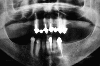

Primero, se hace un estudio completo de la boca para determinar las

necesidades del paciente, para medir la apertura bucal y ver si hay caries y

piorrea no tratadas.

Luego, se saca una placa (radiografía panorámica), para ver si es

posible colocar implantes. A partir de ese momento, se realizan moldes de yeso